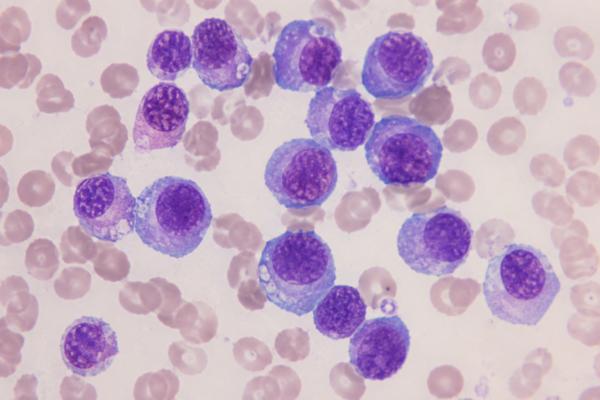

Delve into the intricate world of orthopedic tumors with Dr. Mishil Parikh, a distinguished Tumor Ortho Surgeon in Mumbai. This article offers an in-depth exploration of the causes, symptoms, and risk factors associated with bone tumors, underlining the significance of early detection.

Recent developments in musculoskeletal oncology, highlight Dr. Parikh's commitment to staying at the forefront of medical advancements. Recognize the importance of recognizing early warning signs and symptoms, and discover the peace of mind that comes with having a Bone Tumor Expert nearby.